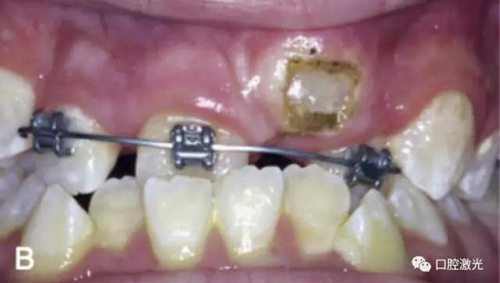

治療前

激光牙齦切割后即刻

粘接托槽

3周后效果